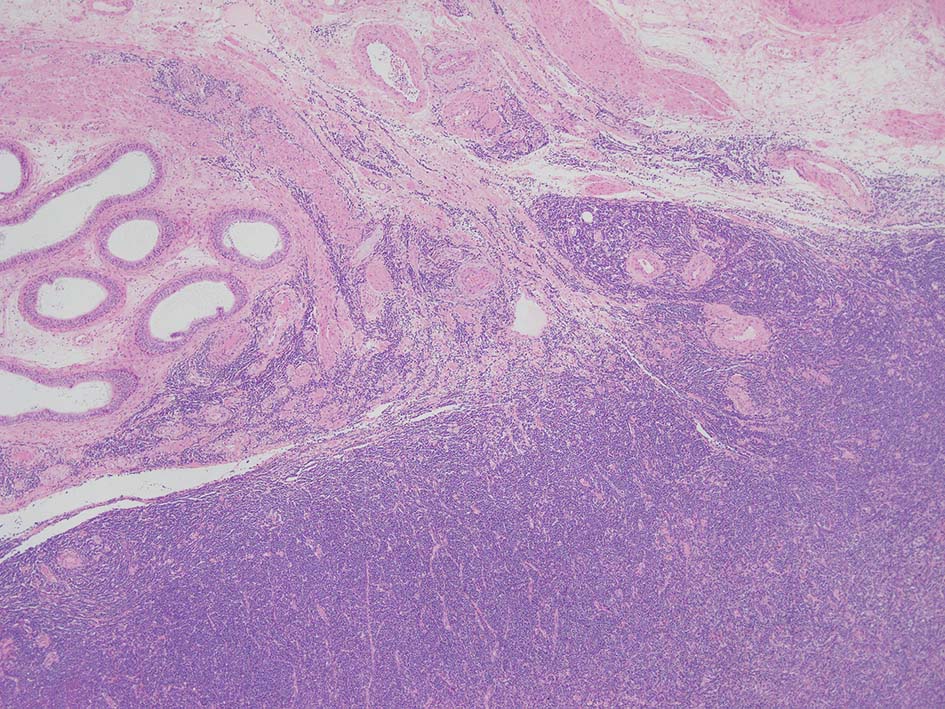

loupe像では, 腫瘍細胞が髄様密に浸潤増殖する部位と, 精細管をスペアするように管間に腫瘍細胞が浸潤する部分(右端図 A)がある.

切り出し図とは天地を逆にした右端図では, 髄様密な部分は白膜内で増殖するリンパ腫瘤(B)であることがわかる. 精巣上体の一部に浸潤がみられる(C)

精巣上体, 精巣周囲脂肪織への浸潤, 精巣実質, 白膜の非浸潤部